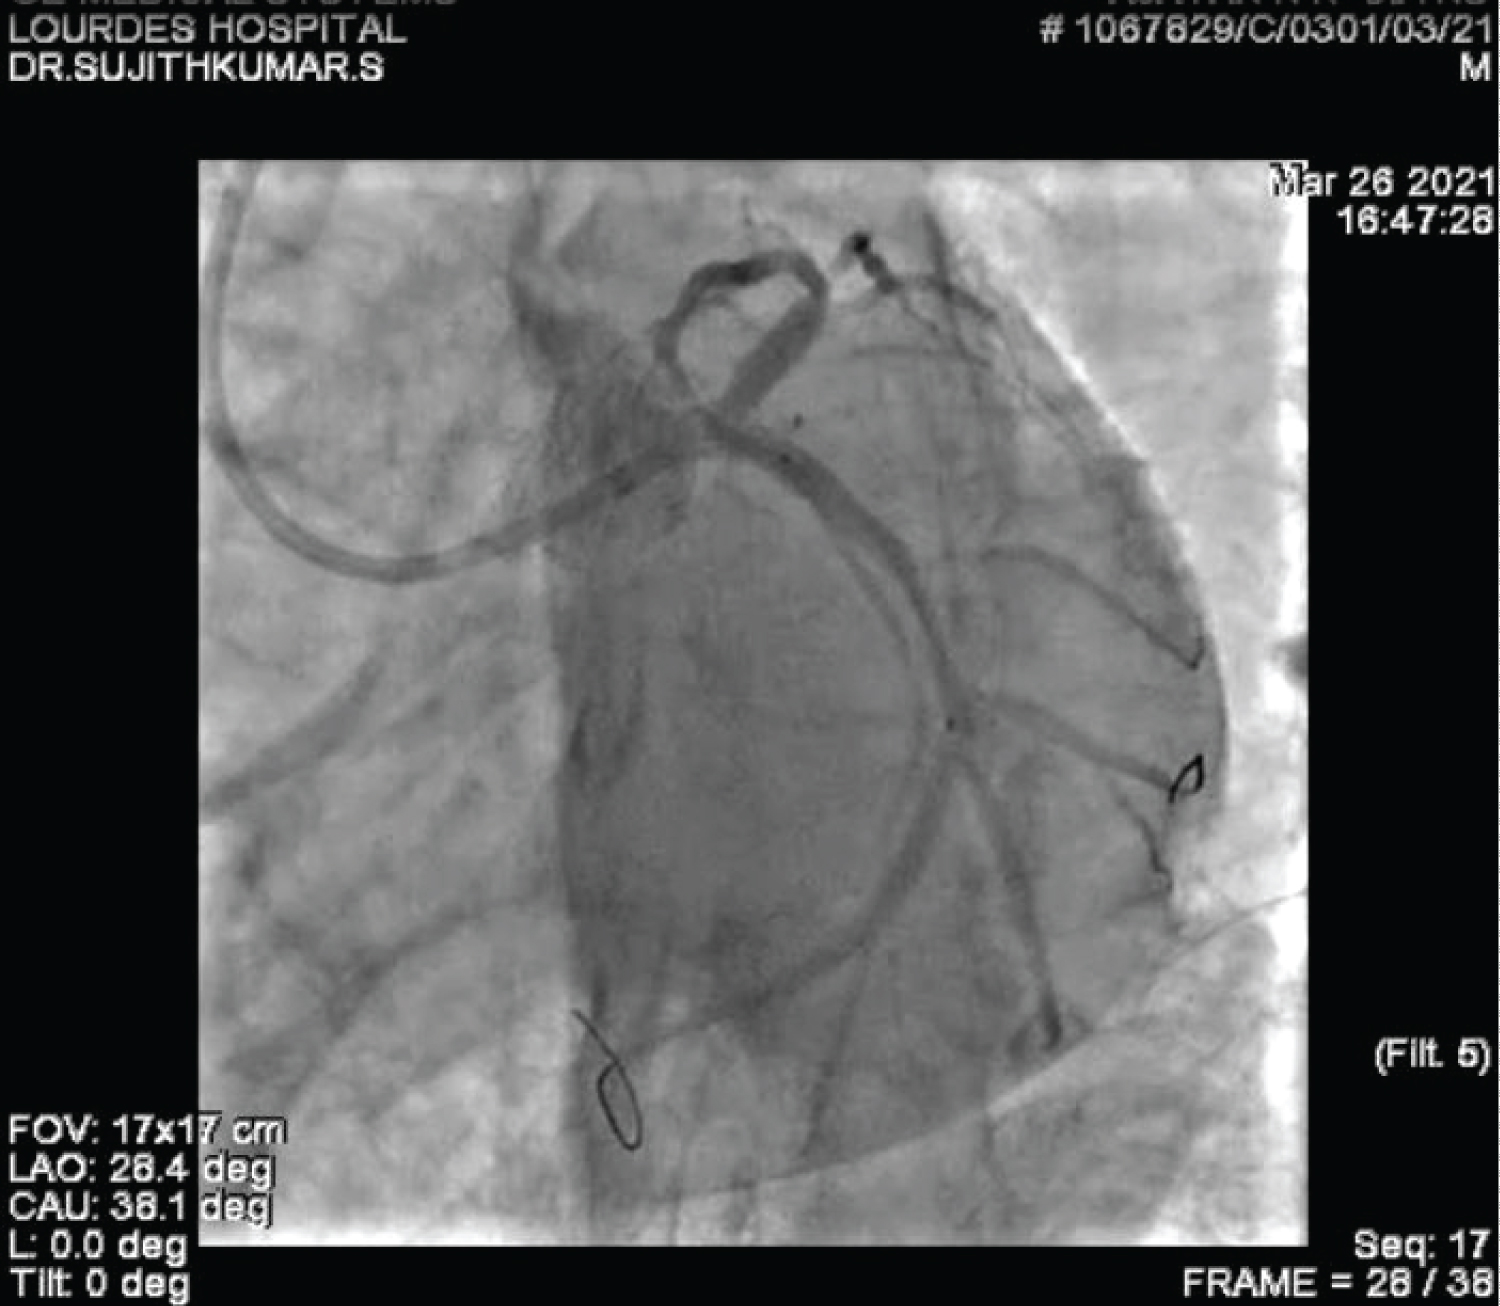

A 60-year-old gentleman was referred to our care with a diagnosis of Inferior Wall Myocardial Infarction, after receiving thrombolytic therapy at a local hospital. ECG, at admission, showed good ST resolution. He was taken up for elective coronary angiogram and revascularization. Coronary angiogram revealed a critical stenosis of dominant Left Circumflex artery (LCX) at Obtuse Marginal artery (OM2) (medina 1,0,1) with TIMI II flow distally (Figure 1 and Video 1). He underwent angioplasty and stenting with a single stent strategy. The LCX was predilated and was stented with a 3 × 24 mm Biomime stent at 14 atmospheres (Figure 2, Figure 3, Figure 4, Video 2 and Video 3). The OM2 was rewired and a dilatation of the ostial lesion of OM2 and kissing balloon inflation was done with excellent result. It was decided to do proximal optimization (POT) to the proximal stent with a 3.25 × 8 mm non-compliant (NC) balloon. But there was difficulty in tracking the balloon down into the stent and fluoroscopy showed a deformation of the proximal edge of the stent which was confirmed by the Stent Viz technology (Figure 5, Figure 6, Figure 7, Video 2 and Video 3). The same NC balloon was then used to post-dilate the stent and the proximal part of the stent was covered with another 3.5 × 13 mm biomime stent with excellent result (Figure 8). After 4 months follow up, the patient is asymptomatic and on dual antiplatelets.

Figure 2: Coronary angiogram in LAO caudal projection showing positioning of the stent in LCX after predilatation (note position of stent in proximal LCX just after the tiny OM vessel). View Figure 2